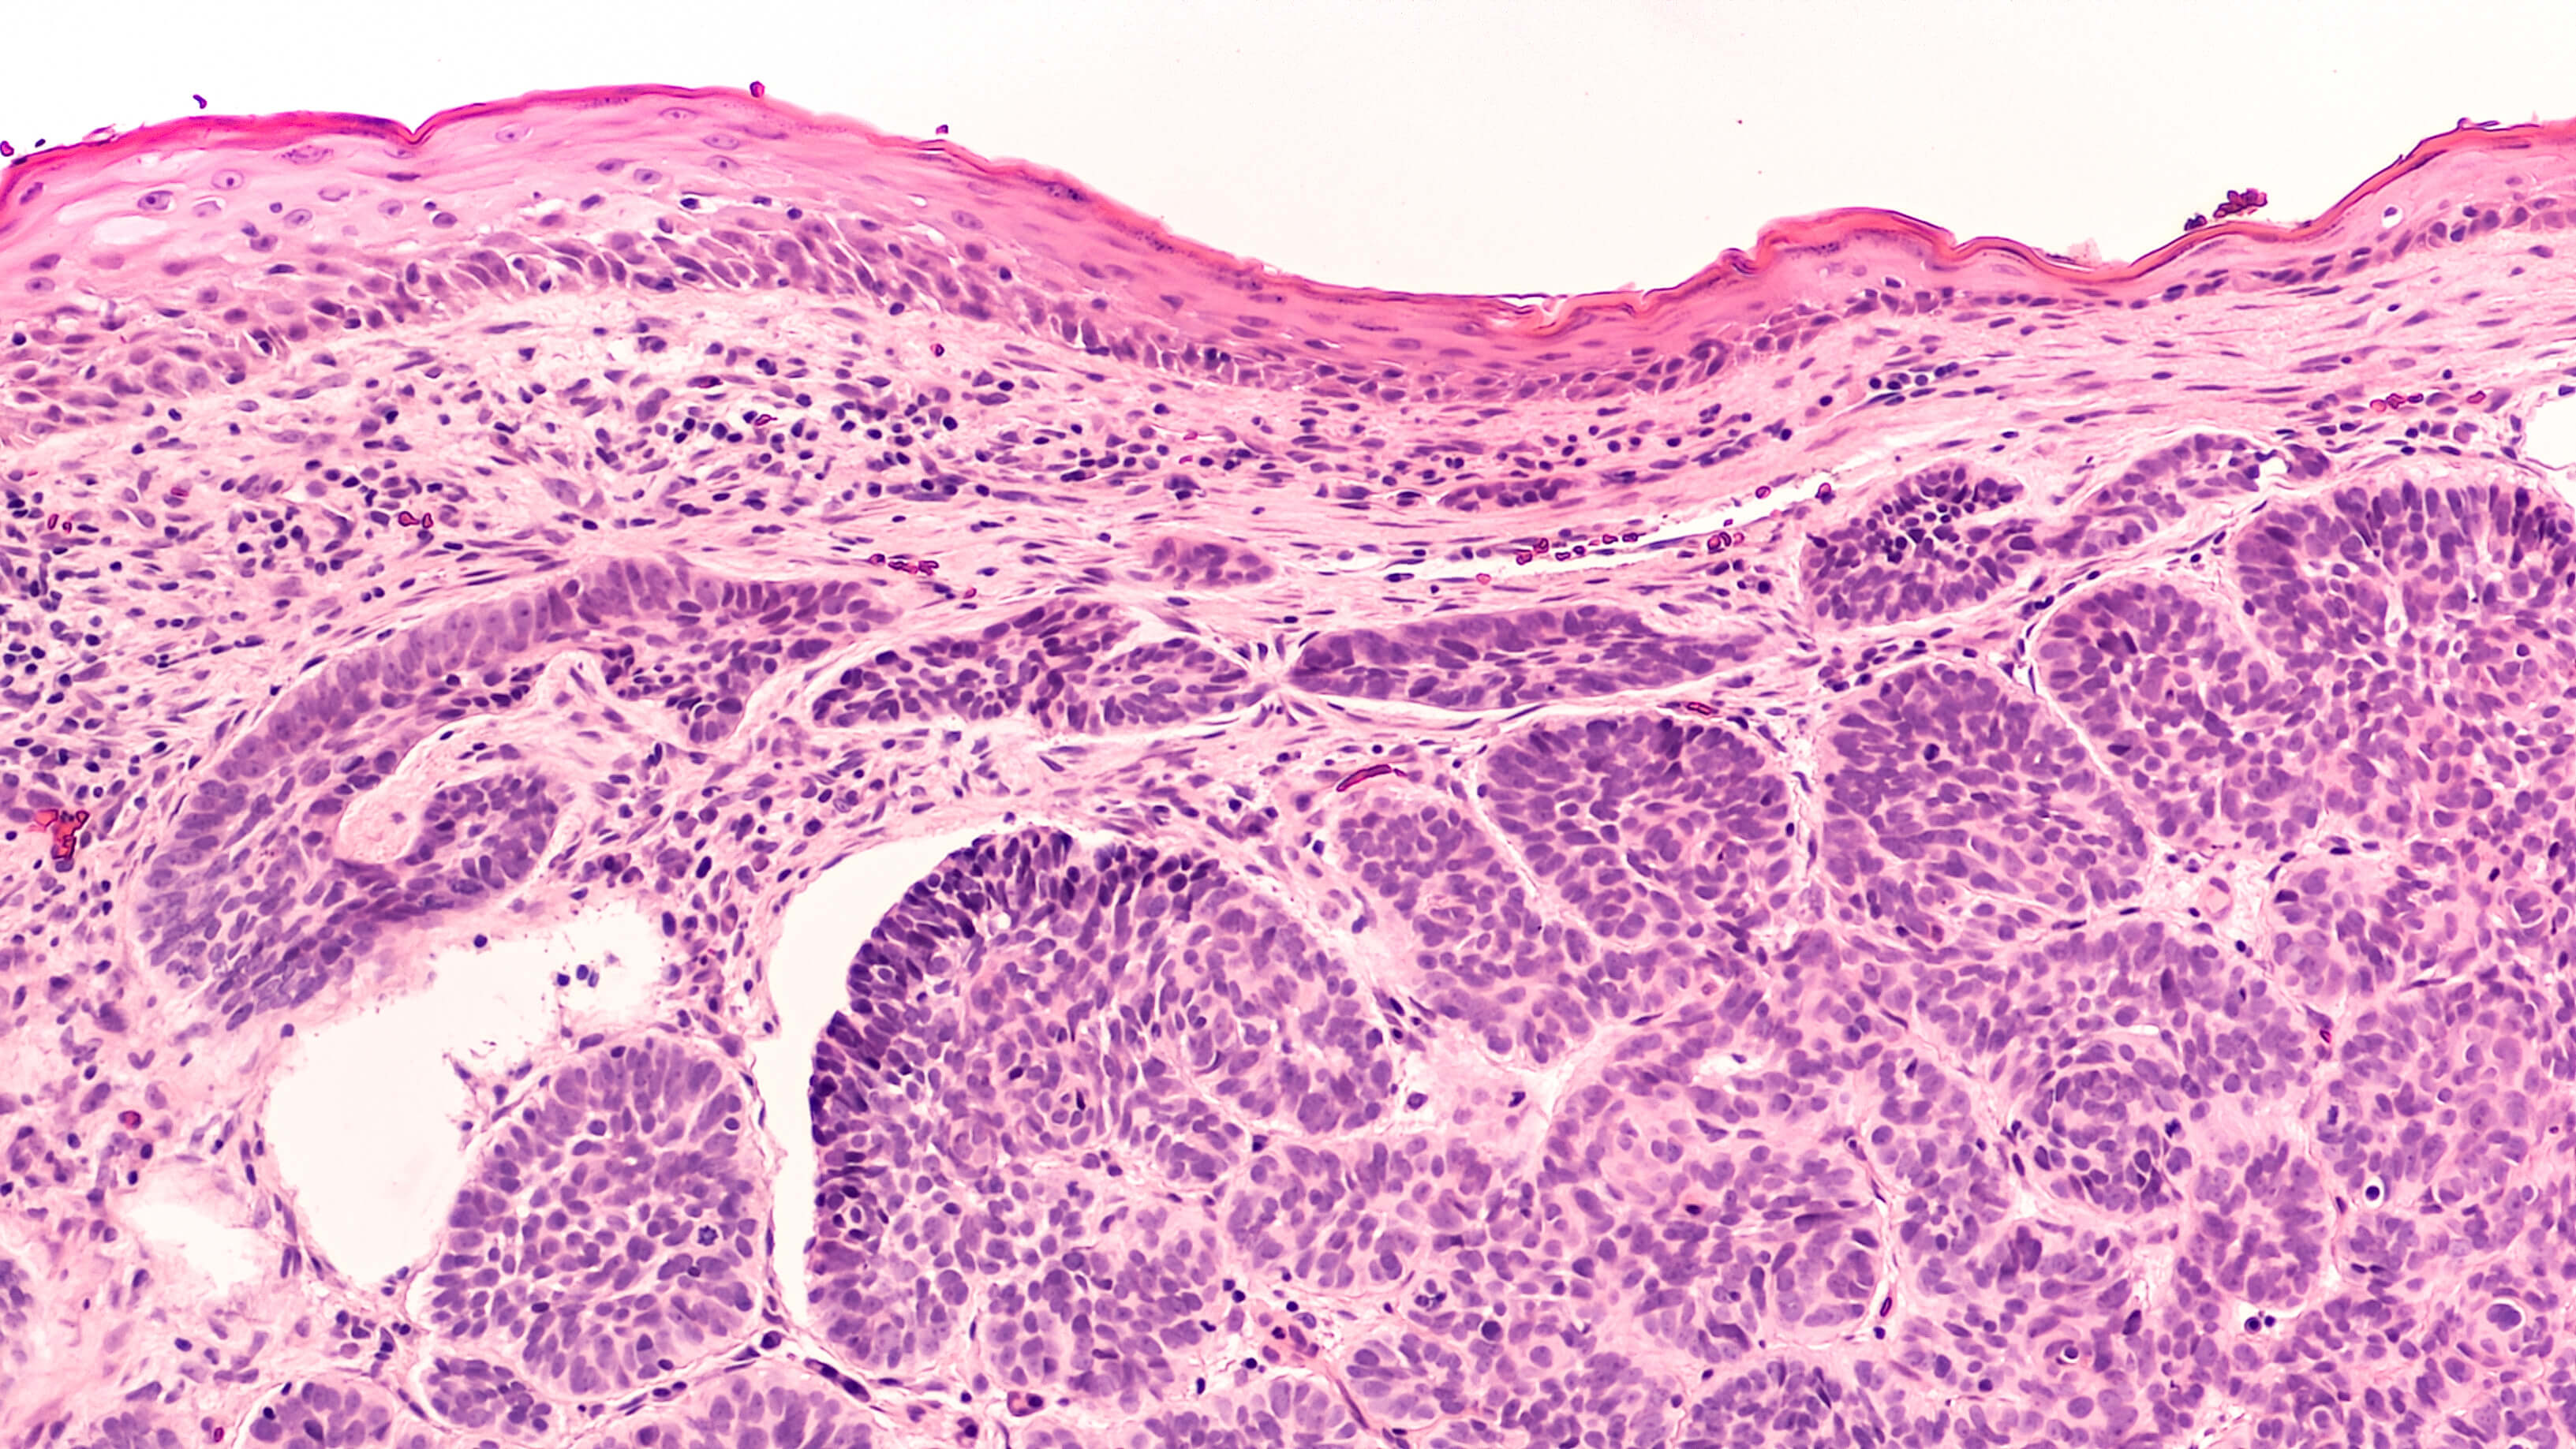

![This image depicts histology of squamous cell carcinoma (SCC). Professional medical imaging for clinical reference and educational purposes. [umbracoNodeId=12918]](/assets/image/jpeg/histology-of-squamous-cell-carcinoma-scc-wcvv4y8bopi8myizbnnaz.jpg)

Histology

SCC is a malignant epithelial tumour of keratinocytes arising most commonly in sun-damaged skin. The vast majority of cases are associated with pre-existing actinic (solar) keratosis, squamous cell carcinoma in situ, or both. SCCs account for nearly 30% of non-melanoma skin cancers.

From a histological point of view, these lesions may be well differentiated, moderately differentiated or poorly differentiated. The degree of differentiation is an essential marker of progression, risk of metastasis and prognosis. Many lesions display areas of varying degrees of differentiation, however, the worst area is to be considered when finally grading the lesion. It is the least differentiated area that ultimately determines the management and prognosis.

SCC with focal basaloid differentiation or basosquamous carcinoma, is regarded as a moderately differentiated lesion. Poorly differentiated SCCs are characterised by the absence of keratinisation. SCC may be slow or fast growing. In some cases, significant clinical changes may be evident within months, or even weeks.